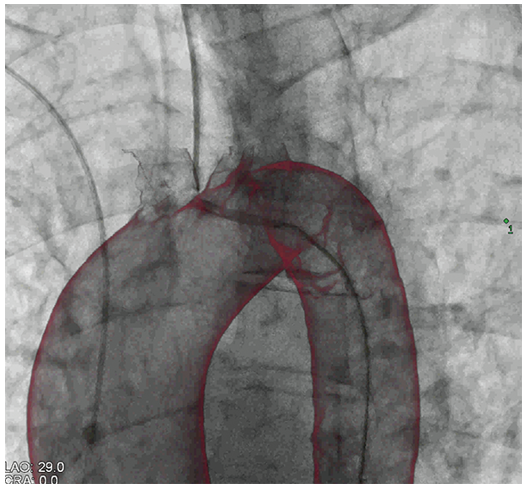

MMF: відновлення аортального клапана

MMF: КТ накладання дуги аорти